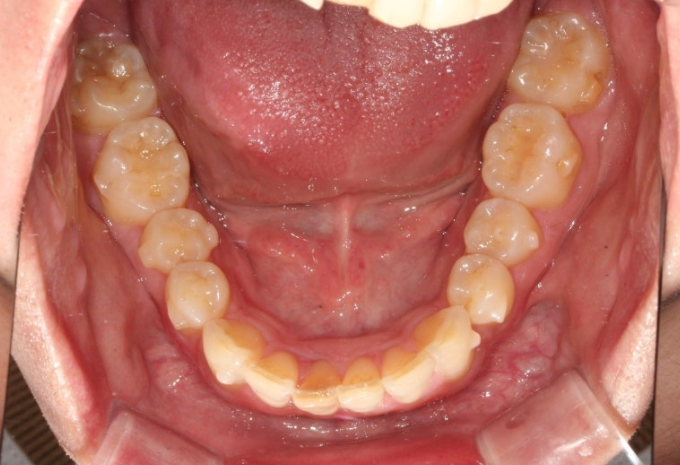

올해 초, 교정치료를 위해 내원한 30대 후반의 환자분입니다.

앞니가 깊게 물리는 과개교합.

중심선 불일치. 정도가 보입니다.

앞니가 많이 뻗쳐있습니다.

위 앞니 뻗침이 심하면 위 아래 앞니 사이 간극이 커지죠.

위아래 어금니 물리는 교합관계는 그래도 1급에 가깝습니다.

악궁모양이 약간 찌그러진 형태입니다.